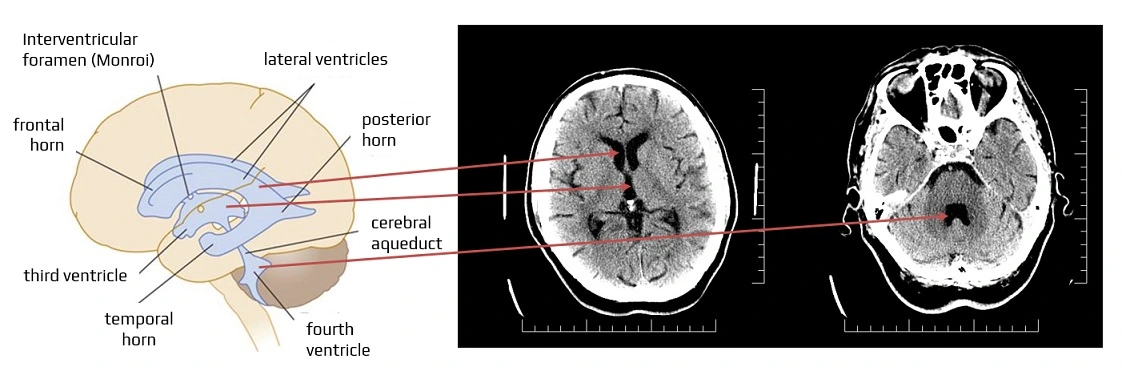

Where are the lateral ventricles located?

In the cerebral hemispheres.

What connects the lateral ventricles to the 3rd ventricle?

Interventricular foramen of Monro.

Where is the 3rd ventricle located?

Between the thalamus

Which structure connects the 3rd to the 4th ventricle?

Cerebral aqueduct of Sylvius.

Where is the 4th ventricle located?

Between the pons and cerebellum.

How does CSF exit the 4th ventricle?

Via lateral and median apertures.